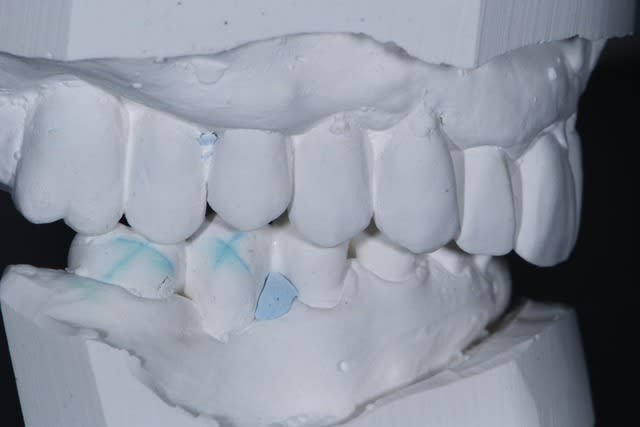

si je pouvais avoir une photo en occlusion et meme mieux une photo en occlusion des modeles en platres ....

Je pense meme a un sur contact de l autre coté.

meme si tu as verifié en oim ou en fonctionnel.....ce n'est pas avec du papier a articuler que tu peux voir si c est bon.

Surtout quand il y a melange dent naturelle et implant.

Photo des moulages de face en occlusion ?

Pas encore réfléchi mais ça m a bien l air occlusal ton affaire.....

Tiens mon lapin!